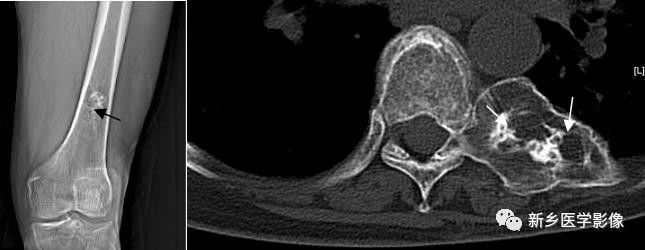

软骨钙化X线、CT图像

a. 股骨下段X线正位片示股骨下段髓腔内多发环形钙化影(↑) b.胸部CT横断面骨窗示左侧肋骨头膨大,内部低密度区内见环形钙化影(↑)